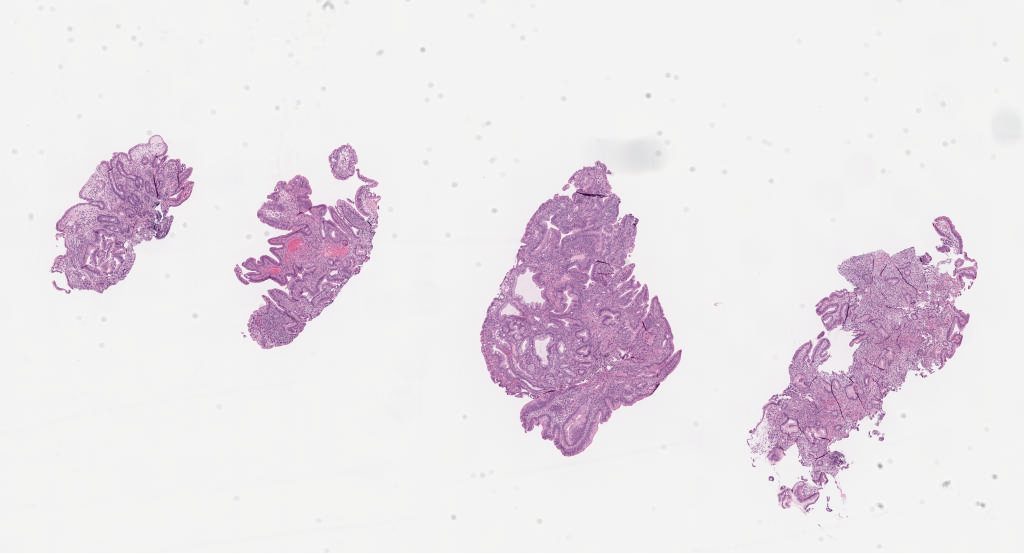

Case14 A.svs

Case14 p53 a.svs

Case14 smad4 a.svs